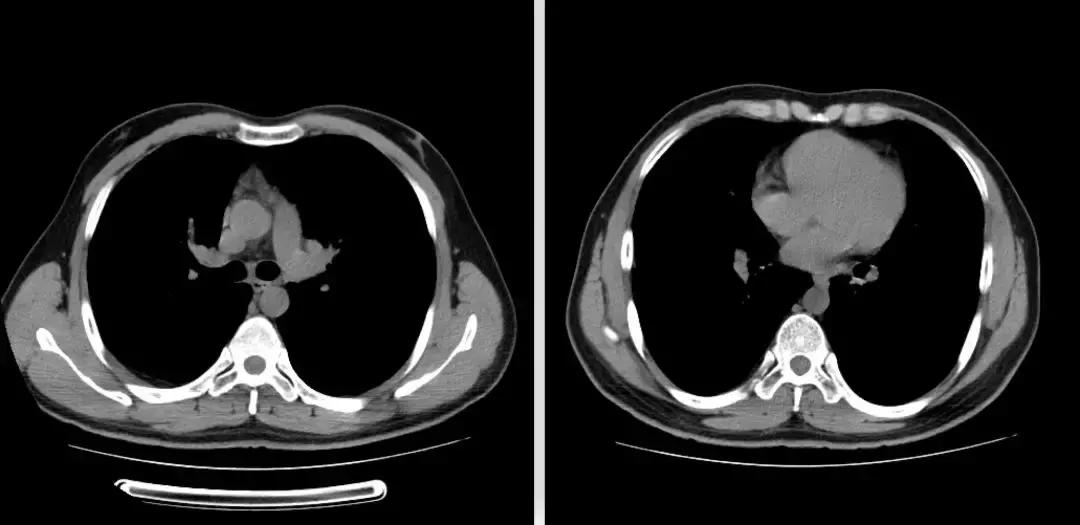

于北京协和医院查相关检查,如下图:

后给予强的松50mg 3月余。

复查胸部CT(2018-07-12):

左肺炎症较前好转,但肺部弥漫性病变较前变化不大。